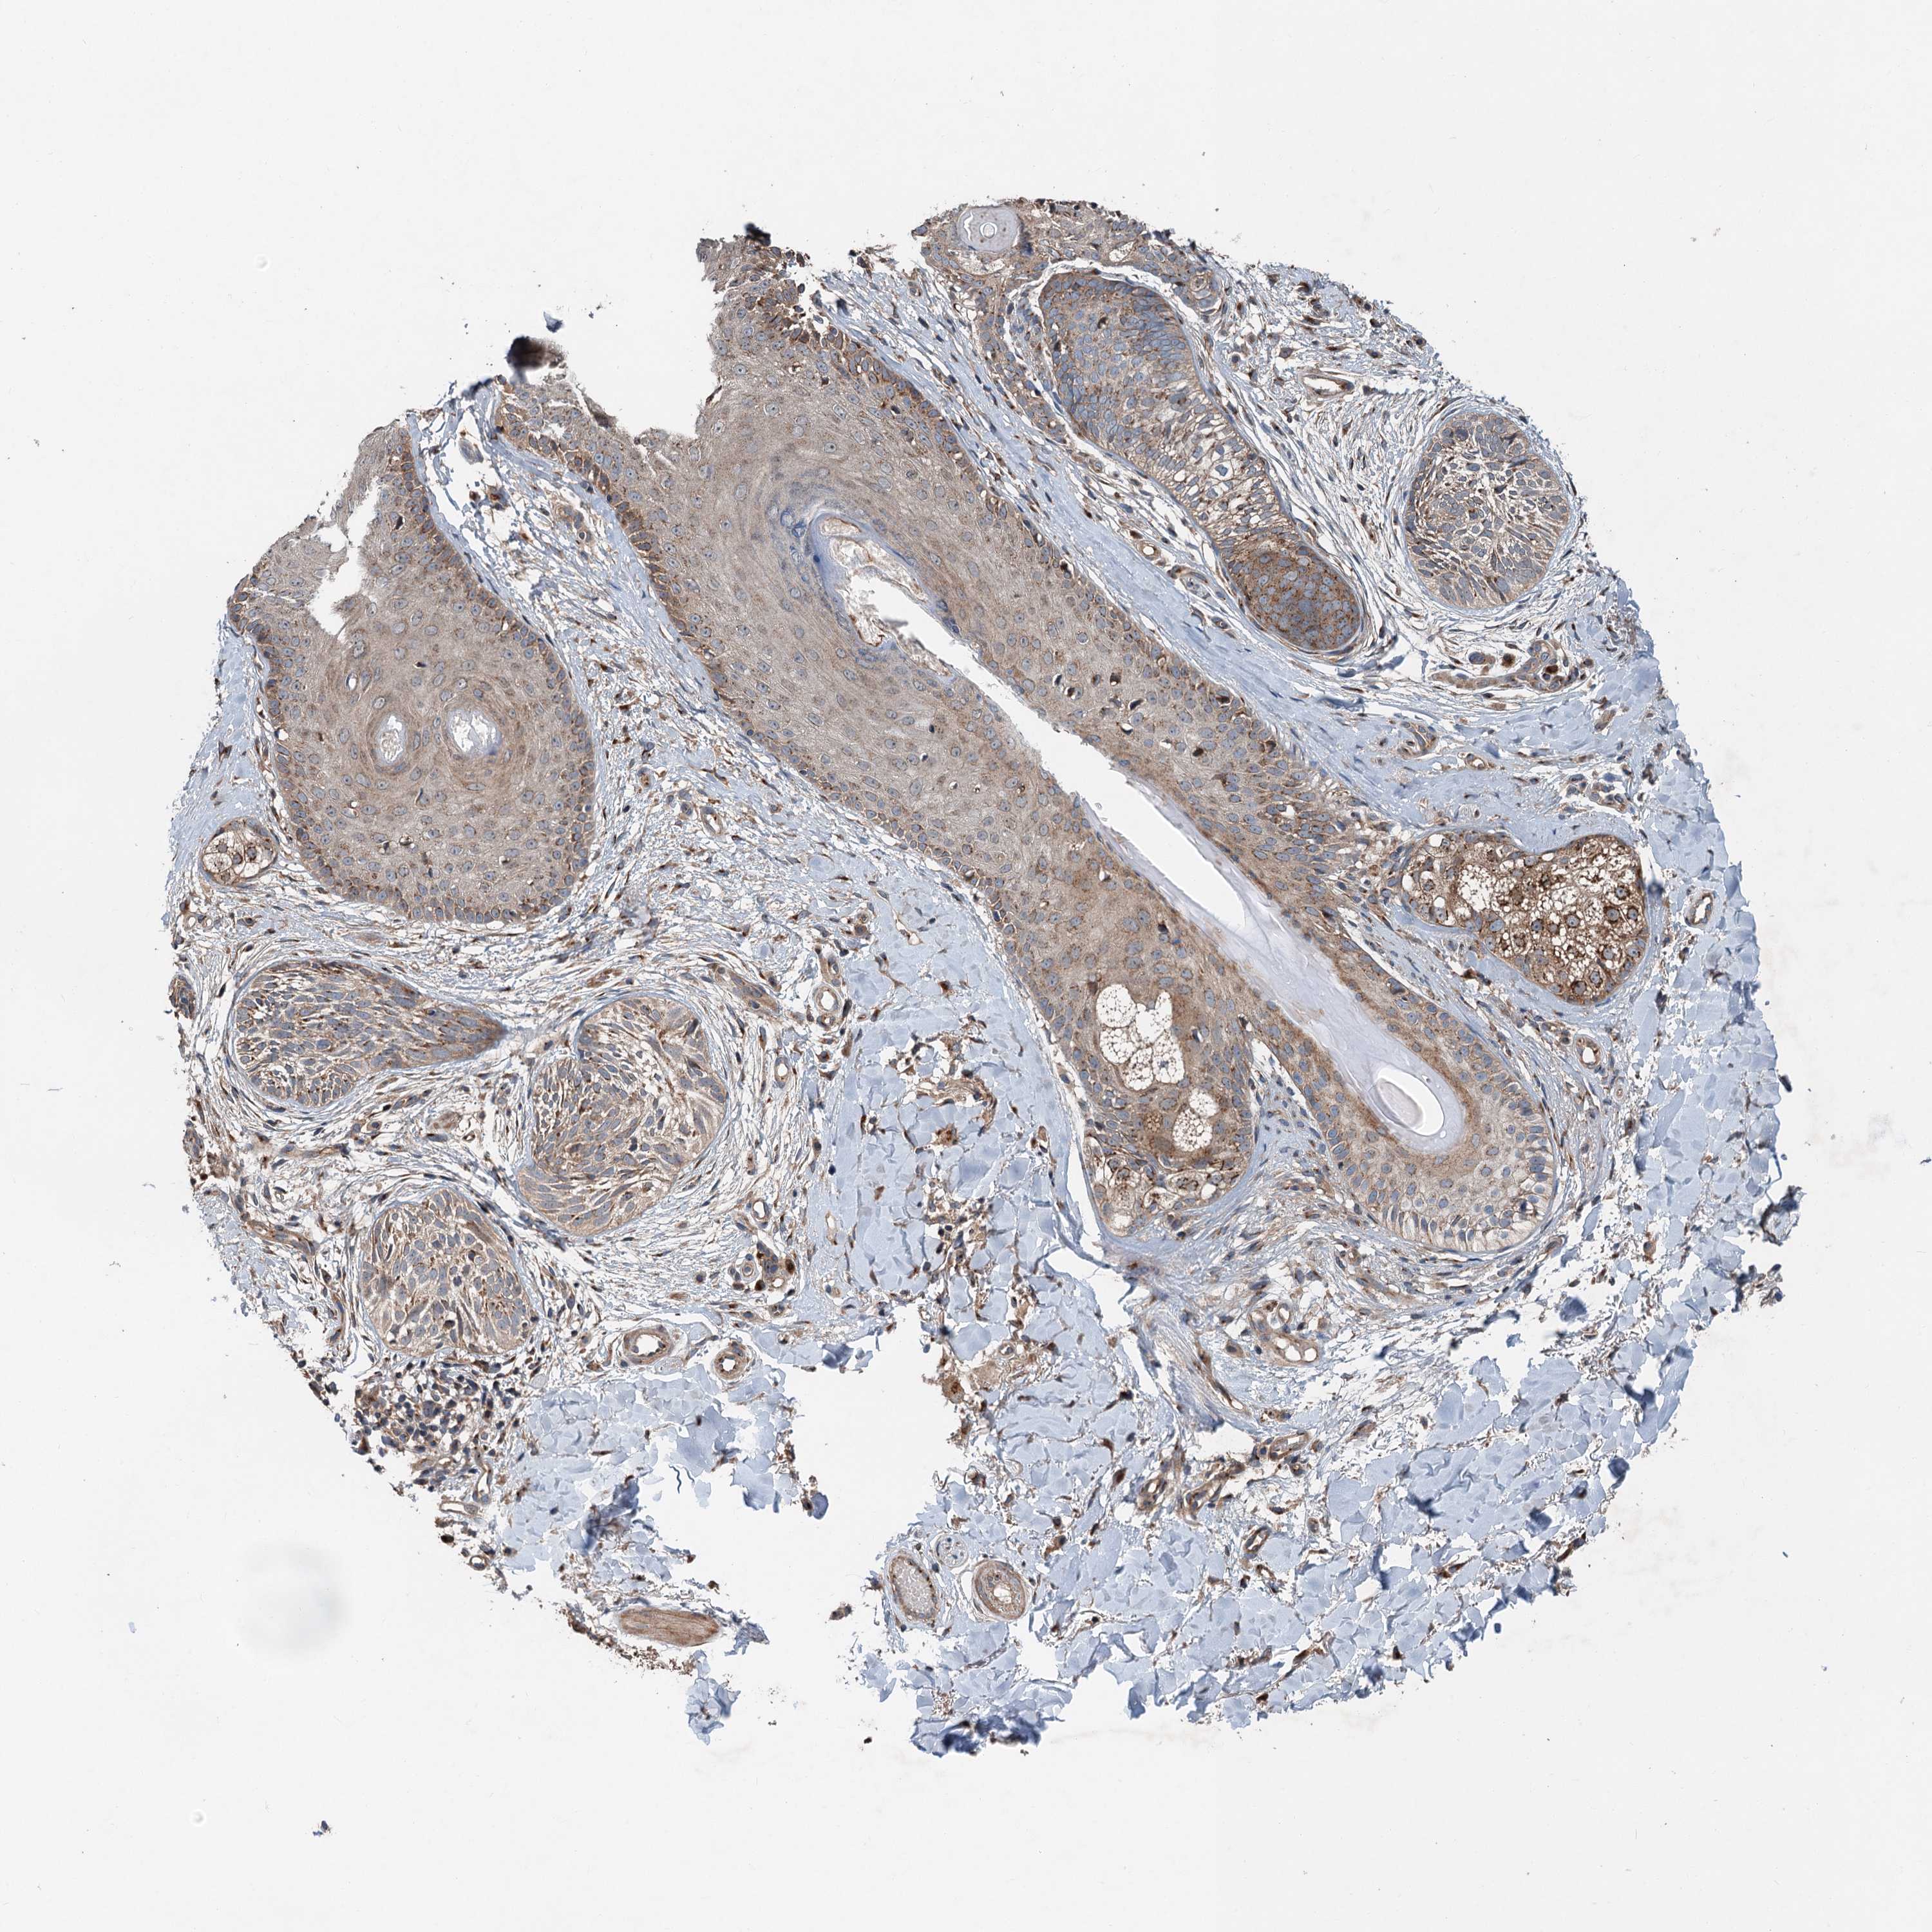

Basal cell and squamous cell cancer

SKIN CANCER - Protein expressioni

A mouse-over function shows sample information and annotation data. Click on an image to view it in a full screen mode. Samples can be filtered based on level of antibody staining by selecting one or several of the following categories: high, medium, low and not detected. The assay and annotation is described here.

Antibody stainingi

Antibody staining in the annotated cell types in the current human tissue is reported as not detected, low, medium, or high, based on conventional immunohistochemistry profiling in selected tissues. This score is based on the combination of the staining intensity and fraction of stained cells.

Each image is clickable and will lead to virtual microscopy that enables deeper exploration of all samples and also displays staining intensity scores, fraction scores and subcellular localization as well as patient and tissue information for each sample.

Antibody HPA040353

Staining

Medium

Intensity

Moderate

Quantity

75%-25%

Location

Cytoplasmic/membranous

Squamous cell carcinoma, NOS